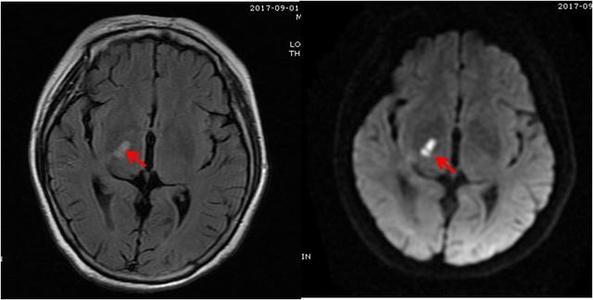

双侧侧脑室旁腔隙性脑梗塞

病灶部位在双侧脑室旁。腔隙性脑梗死是脑梗死的一种。只是因为发生闭塞的血管较小,如穿支动脉,限于其较小的供血区... 腔隙性脑梗死是脑梗死的一种...

双侧侧脑室体旁腔隙性脑梗塞

两侧脑室旁腔隙灶是怎么回事?

病情分析: 你好,根据你的描述,应该是指两侧脑室旁有腔隙性的脑梗死病灶,腔隙性梗死是指大脑半球或脑干深部的小穿通动脉,在长期高血压病的基础上...